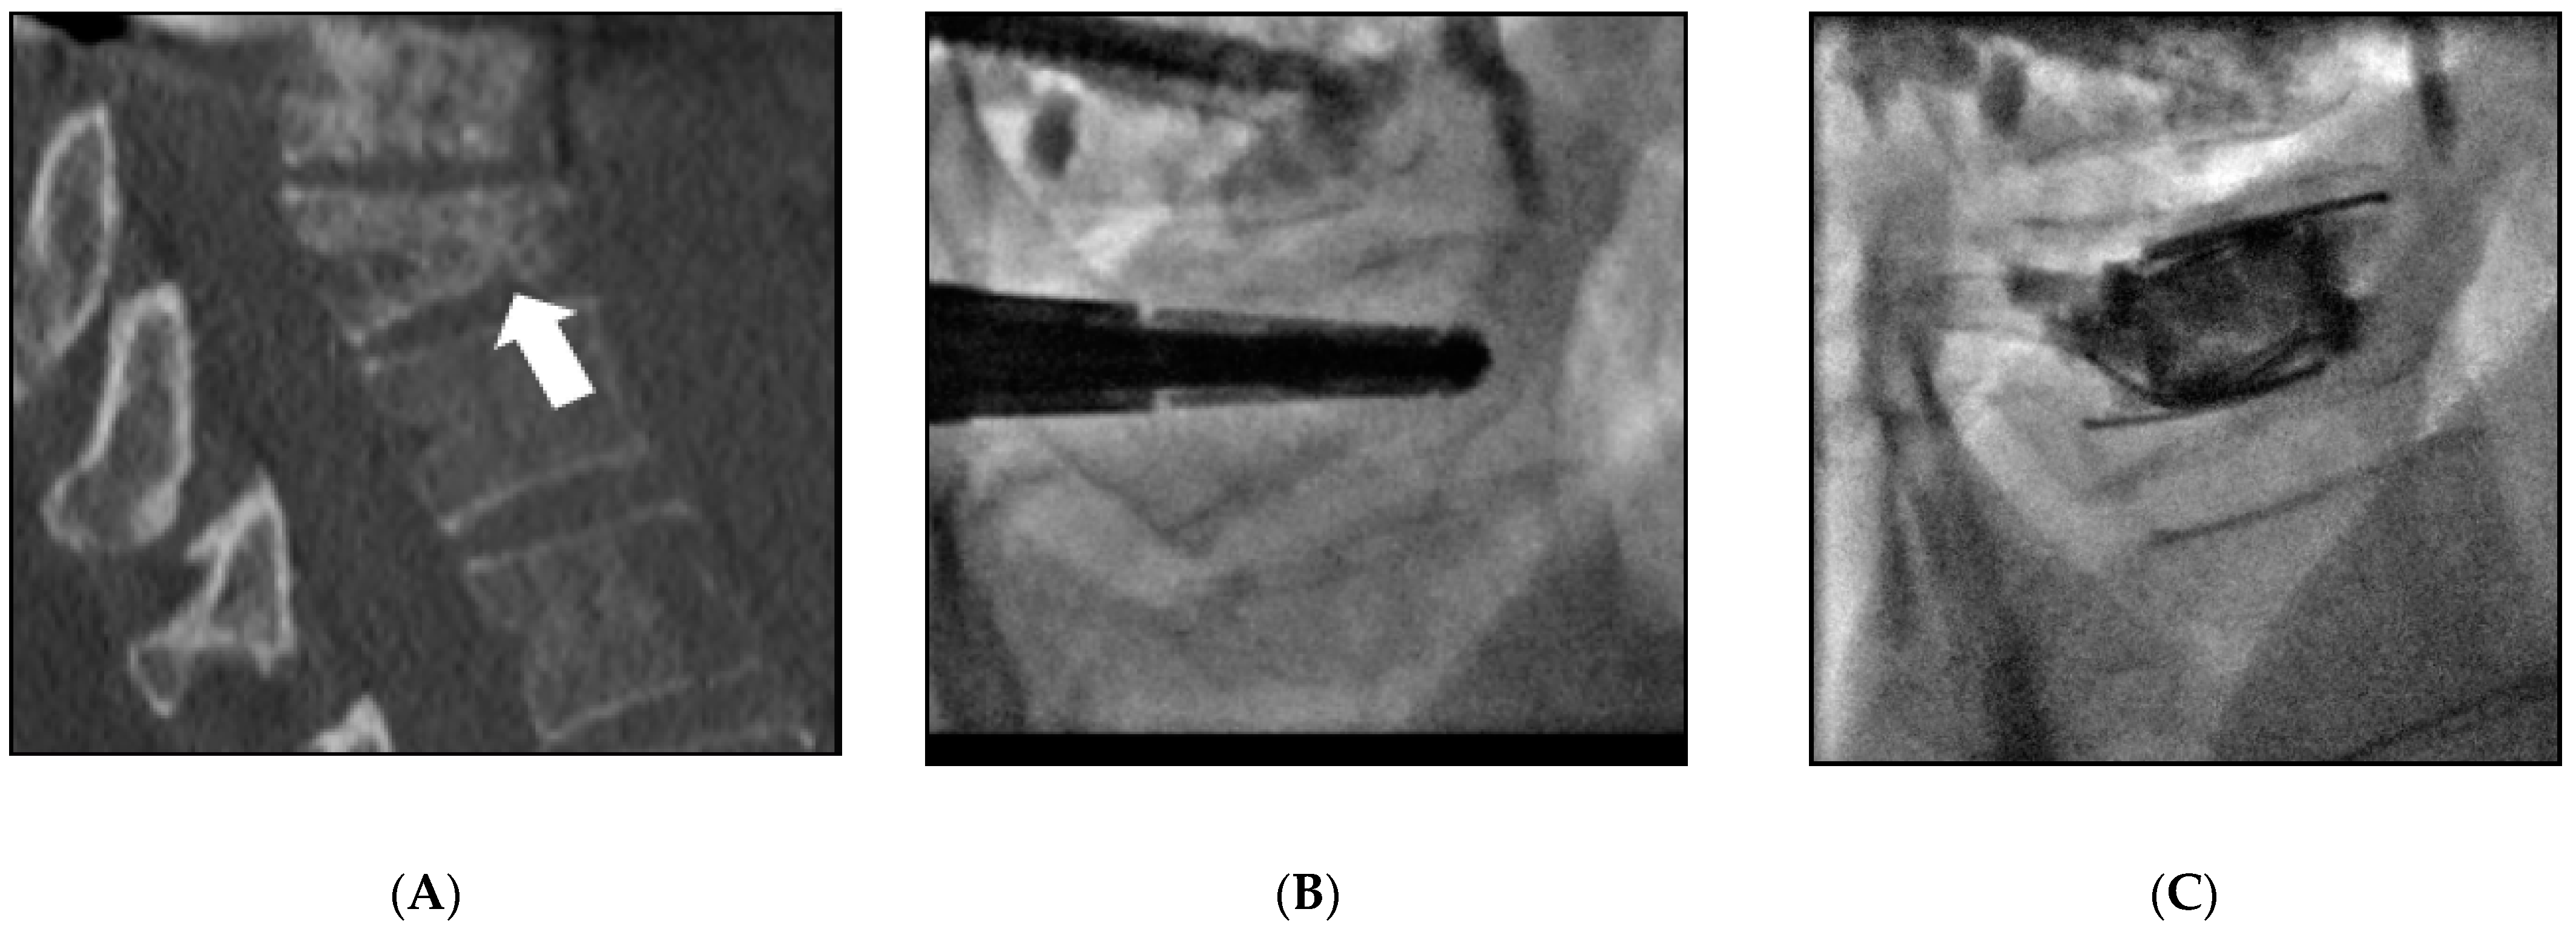

| 1 | 59 | Female | Breast | L2 | 10 | V-strut® (2) | Electrochemotherapy | L2 | Cement leakage (1) | - |

| 2 | 53 | Female | Breast | L4 | 8 | V-strut® (2) | - | - | - | - |

| 3 | 64 | Male | Lung | L2 | 9 | V-strut® (2) | Vertebroplasty | L3 | VCF L4&L5 (2) Cement leakage (1) | Vertebroplasty |

| 4 | 58 | Male | Lung | L4 | 9 | V-strut® (2) | - | - | Cement leakage (1) | - |

| 5 | 54 | Female | Breast | L4 | 10 | V-strut® (2) | Vertebroplasty | L3 | VCF L5 (2) Cement leakage (1) | - |

| 6 | 48 | Male | Lung | L1&L4 | 9 | SpineJack® (4) | Vertebroplasty | T9 T10 T11 T12 | - | - |

| 7 | 62 | Male | Lung | L3 | 9 | SpineJack® (2) | Vertebroplasty | T2 T3 T4 | - | - |

| 8 | 40 | Female | Breast | T8 | 7 | SpineJack® (2) | - | - | - | - |

| 9 | 73 | Female | Breast | L1 | 10 | SpineJack® (2) | - | - | VCF L2 (3) Cement leakage (1) | Spinejack® (2) |

| 10 | 56 | Female | Ovarian | T12 | 12 | SpineJack® (2) | Vertebroplasty | T10 T11 L1 | - | - |

| 11 | 79 | Female | Lung | L1&L2 | 01 | SpineJack® (4) | - | - | - | - |

| 12 | 23 | Female | Osteosarcoma | T12&L1 | 9 | SpineJack® (2) | Vertebroplasty | C7 T3 T5 | Cement leakage (1) | - |

| 13 | 89 | Female | Ovarian | T11&L1 | 10 | SpineJack® (2) | Vertebroplasty | T12 | - | - |

| 14 | 74 | Female | Ovarian | T12&L1 | 10 | SpineJack® (4) | Vertebroplasty | L2 | Cement leakage (1) | - |

| 15 | 59 | Female | Breast | T9 | 9 | Kiva® (1) | - | - | - | - |

| 16 | 57 | Male | Myeloma | L2 | 7 | Kiva® (1) | - | - | - | - |

| 17 | 78 | Male | Lung | T12 | 7 | SpineJack® (2) | Vertebroplasty | T3 T4 | - | - |

| 18 | 49 | Female | Breast | T10 | 7 | Spinejack® (2) | - | - | - | - |